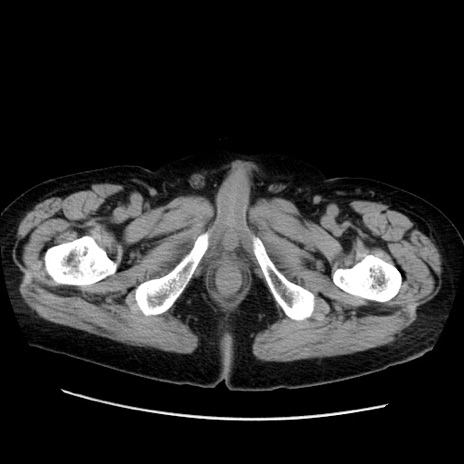

症例21(横断像)

【症例】70歳代男性

【主訴】腹痛

【現病歴】肝硬変・肝細胞癌にてかかりつけの方。約9時間前に食後より腹痛出現。症状が徐々に増悪し、嘔吐出現したため来院。

【既往歴】肝硬変、肝細胞癌(RFA、TACE後)

【身体所見】意識清明、表情苦悶様、BT 36℃、BP 129/78mmHg、P 88bpm、SpO2 97%(RA)、右上腹部から心窩部にかけて圧痛あり、反跳痛なし、筋性防御あり。

【データ】WBC 5800、CRP 0.16